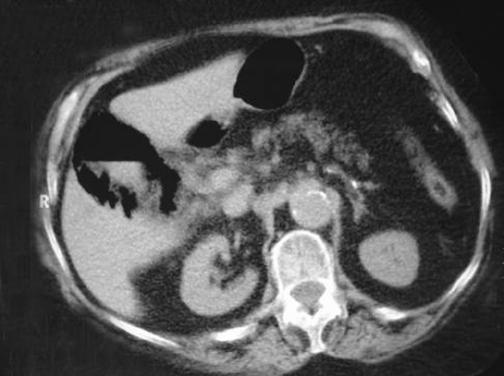

An 83-year-old female patient was admitted to the hospital with acute abdominal syndrome. Clinical examination and blood tests suggested acute cholecystitis. Plain radiography revealed a circular gas pattern in the right upper quadrant suggestive of emphysematous cholecystitis. Subsequent computed tomography confirmed the presence of gas in the gallbladder wall and a gas-fluid level within the organ.

一名83岁女性患者因急性腹部综合征入院。临床检查和血液检查提示急性胆囊炎。腹部平片显示右上腹有圆形气体影,提示气肿性胆囊炎。随后的计算机断层扫描证实胆囊壁内有气体,胆囊内有气液平面。